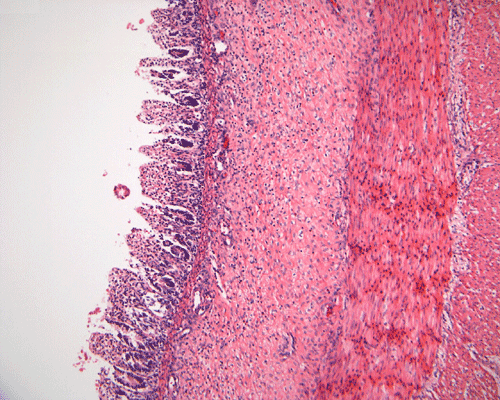

Discussion of the pathology is limited to the alimentary canal. On autopsy, the intestinal loops are largely dilated with gas accumulation. On closer examination, many small, subserosal bubbles can be seen (arrows in Panel A). The intestinal wall is also thinned out as a result of the dilatation by gas (Panel B). In the less affected areas, the intestinal  wall is not thinned out and the mucosa can still be recognized as largely intact (with autolytic changes) (Panel C and E). In the thinned out areas, the mucosa appear pink and necrotic (Panel D, F and G). The subserosal bubbles appear to be empty vesicles filled with air and they are found most frequently in the most necrotic region. In general, these features indicate widespread infarction with gas production (Panel H and I).

Coagulative and hemorrhagic necrosis is the key pathologic feature of NEC.  Necrosis is limited to the mucosa in the early stages but at least focally transmural in specimens removed from surgical resection or at autopsy.  In 10% of cases, focal necrotic pseudomembrane formation is seen.

A mixed acute and chronic inflammatory infiltrate is commonly found, limited to the mucosa in some foci but transmural in others.  Inflammation and necrosis often occur together in a given segment, but in some instances, one or the other may predominate.